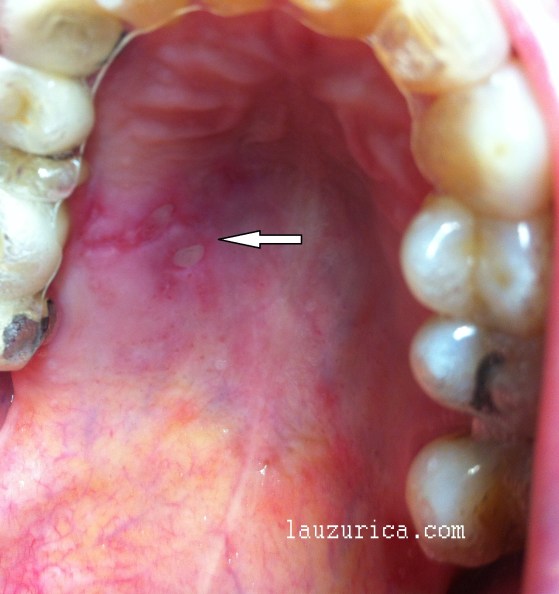

Aftas en el paladar

La mayoría de las veces el asiento de las aftas es en el epitelio no queratinizado, mucosa de boca y labios, también la lengua, y más raro en paladar o encías.